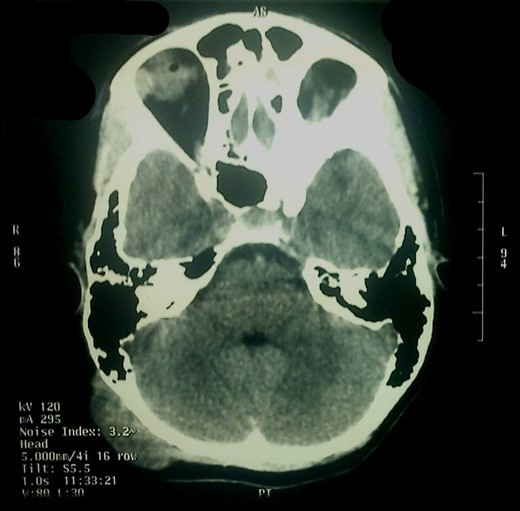

Α 12-year-old girl presented to us with a painless tumefaction on the right suboccipital region evolving for 5 months. Clinical examination did not reveal any other important symptoms or signs. Various explorations carried out, in particular, X-rays (Fig. 1), CT scan with intravenous contrast medium (Figs 2 and 3) and imagery by magnetic resonance with intravenous paramagnetic contrast.

The CT scan showed that there was only thinning of the bone without erosion or intracranial extension of the mass. There were no signs of calcification, and there was a mild and inhomogeneous uptake of the contrast.